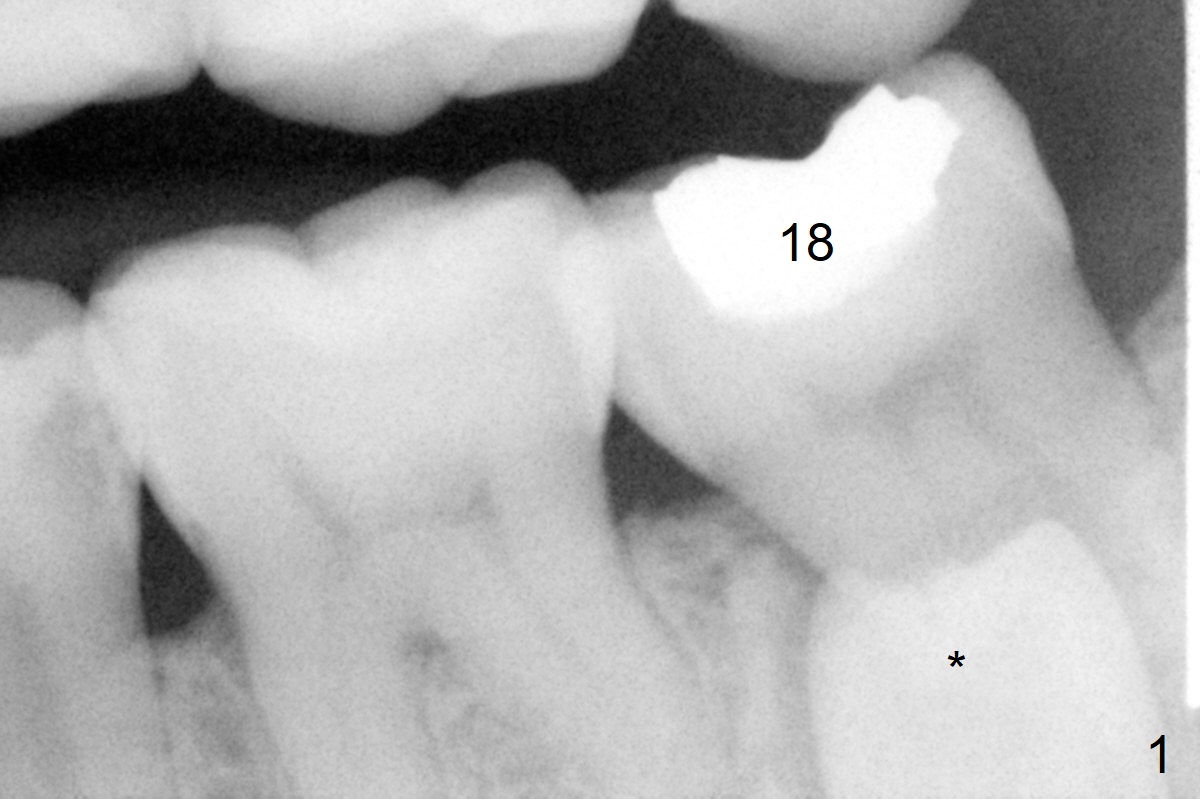

A 45-year-old woman with severe crowding (Fig.2) presented to my office 9 years ago; the tooth #18 appears to have root resorption, most likely due to a supernumerary tooth (Fig.1 *). The latter seems to be erupting in 6 and 9 years (Fig.2,3), probably because of immature apex (Fig.2, as compared to the supernumerary tooth in the lower right (*)). Recently the patient has transient sensitivity at #18. The tooth has mobility I without deep periodontal pockets. If the tooth #18 turns to be non-salvageable, what should be done? The tooth #20 has received root canal therapy, while the tooth #29 has had RCT retreat.